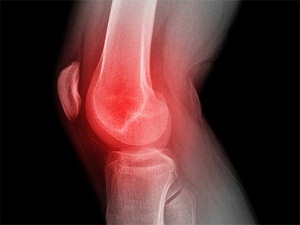

Çocuklardaki diz ağrılarını hafife almayın